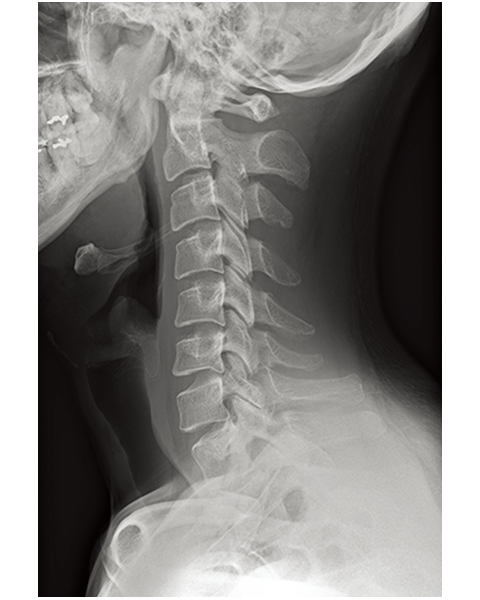

Multiple body parts supported

Cervical Spine